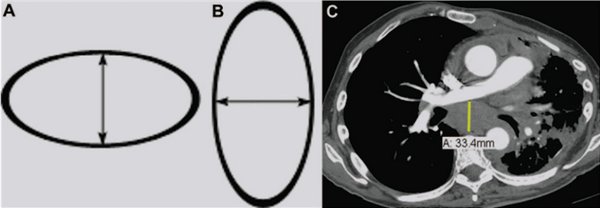

На схеме a и b представлены примеры измерения горизонтально и вертикально расположенных лимфатических узлов, как Вы заметили измерение лимфатического узла производится по короткой оси.

На постконтрастной КТ (изображение C) представлен лимфатический узел субкаринальной группы, усиливающийся постконтрастно, в коротком измерении который составляет 33.4 мм.